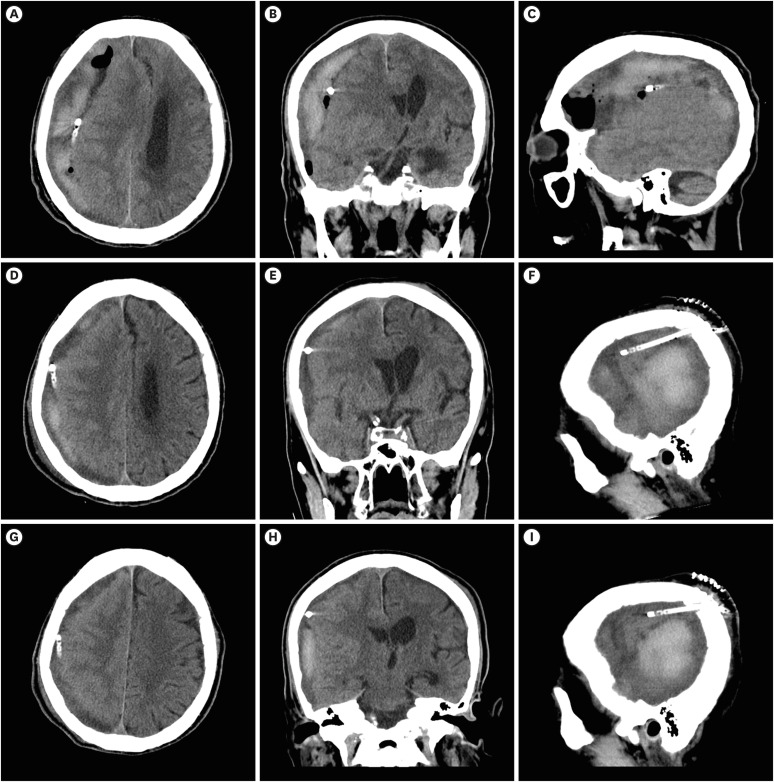

本文报告一位89岁的亚急性硬膜下血肿(SDH)患者,通过钻孔穿刺(BHT)和硬膜下引流放置局部麻醉治疗,随后使用纤维蛋白溶解剂组织纤溶酶原激活剂(tPA)液化血肿。最初,患者表现为急性创伤后SDH,无神经系统症状,给予保守治疗。大约一周后,患者出现偏瘫并进展为昏迷状态。影像学证据显示亚急性SDH已演变为慢性阶段,肿块效应增加,导致新的神经功能缺损。虽然考虑开颅手术,但在护理人员的要求下没有进行全身麻醉。BHT后,放置硬膜下导管,但最初的引流很少。然后给予tPA以促进液化和排水。脑部后续电脑断层扫描证实血肿有明显引流。患者随后恢复意识和运动功能。本报告讨论了一种微创治疗亚急性SDH的方法。我的方法是结合BHT和纤溶治疗,使用tPA,以最小的手术干预有效地清除血肿。在这里,我提出了一个使用tPA的病例,详细介绍了纤维蛋白溶解治疗的方法、影像学发现和临床结果。

This report presents an 89-year-old patient with subacute subdural hematoma (SDH) treated with local anesthesia via burr-hole trephination (BHT) and subdural drain placement, followed by liquefaction of the hematoma using the fibrinolytic agent, tissue plasminogen activator (tPA). Initially, the patient presented with acute post-trauma SDH without neurological symptoms, for which conservative treatment was administered. About a week later, the patient developed hemiplegia and progressed to a stuporous state. Radiographic evidence indicated that the subacute SDH had evolved into a chronic stage with an increased mass effect, causing new neurological deficits. Although craniotomy was considered, general anesthesia was not performed at the caregiver's request. After BHT, a subdural catheter was placed, but initial drainage was minimal. tPA was then administered to promote liquefaction and drainage. Follow-up computed tomography of the brain confirmed significant drainage of the hematoma. The patient subsequently recovered consciousness and motor function. This report discusses a less-invasive alternative for managing symptomatic subacute SDH. My approach of combining BHT with fibrinolytic therapy using tPA facilitated effective evacuation of the hematoma with minimal surgical intervention. Here, I present a case where tPA was used, detailing the methodology, imaging findings, and clinical outcomes of fibrinolytic therapy.